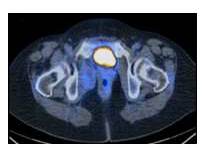

Paciente de 55 años, FUR: 43 años, I gestas, I cesárea, con antecedentes de hipertensión arterial controlada, cáncer de mama derecha, quien es referido por especialista (oncólogo) posterior a realizar CT-PEP control evidenciando LOE pélvico (Figura 1). Es evaluada evidenciándose al examen físico sin alteraciones, se solicita TC abdominopélvica con doble contraste que reporta: masa heterogénea a nivel de músculo isquiorectal derecho, sólido, con áreas de necrosis (Figura 2). Se solicitan paraclínicos: sin anteraciones + citología de cérvix: normal. Se realiza intervención quirúrgica en Clínica la Floresta donde se logra la exéresis de tumoración en su totalidad + toma de muestra de fondo de saco anterior y posterior. El resultado reportó: leiomioma. La paciente actualmente con control ecográfico cada 6 meses sin alteraciones durante su primer año, luego control anual, se encuentra libre de enfermedad a los 6 años de tratamiento.